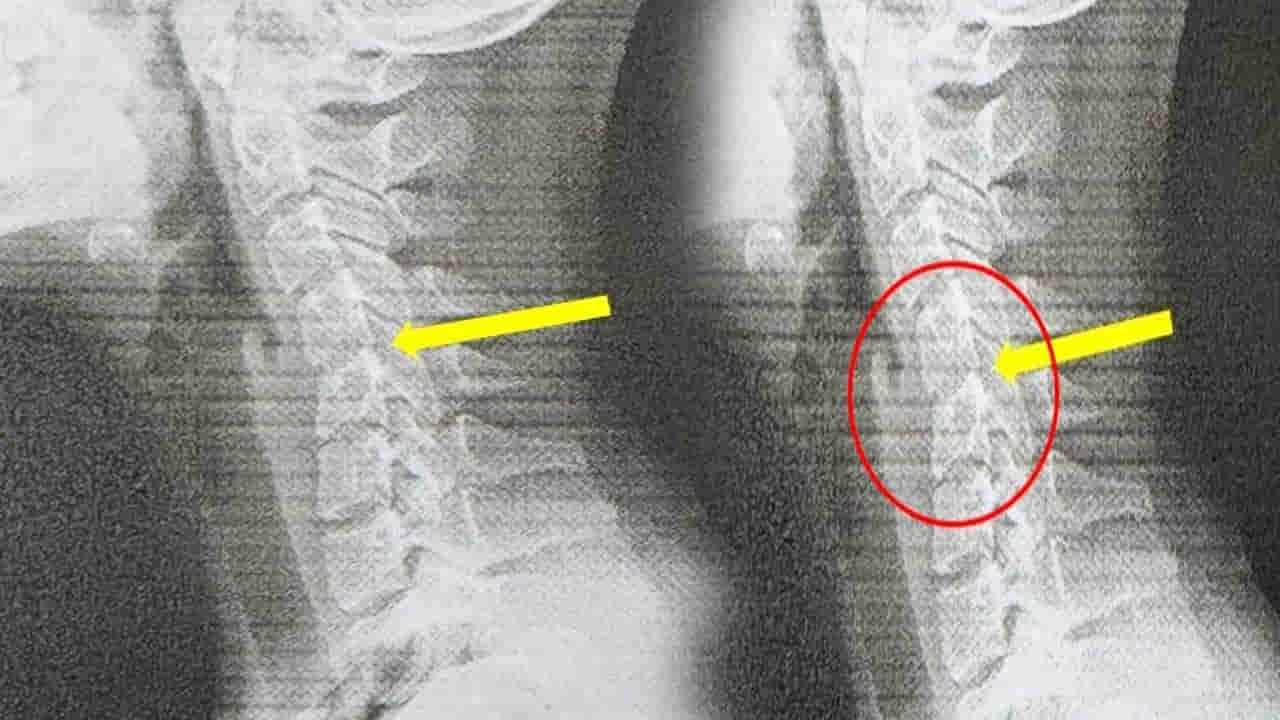

20 ఏళ్ల యువతి అతిగా ఫోన్ వాడటం వల్ల.. ఆమె మెడ 60 ఏళ్ల వృద్దుడిలా మారిపోయింది. ఆమెకు టెస్టులు చేసిన వైద్యులు.. అతిగా ఫోన్ వాడటం వల్ల ఇది జరిగిందని నిర్ధారణకు వచ్చారు. తనకు తరచూ తలనొప్పి వచ్చేదని.. మెడ రాయిలా మారిపోవడమే కాదు.. వలిపోయిందని డాక్టర్కు చెప్పుకొచ్చింది. హుటాహుటిన డాక్టర్లు CT స్కాన్ తీయగా.. అందులో షాకింగ్ విషయం వెల్లడైంది. ఆమె గర్భాశయ వెన్నుముక తన సహజ ఆకృతిని కోల్పోగా.. కొన్ని ప్రాంతాల్లో వెన్నుపూస జారిపోయిన సంకేతాలు కూడా డాక్టర్లు గుర్తించారు.

మెడను 60 డిగ్రీలు వంచడం సాధారణ స్మార్ట్ఫోన్ భంగిమ.. ఇది గర్భాశయ వెన్నెముకపై దాదాపు 27 కిలోల భారాన్ని మోపుతుందని డాక్టర్ యే వివరించారు.ఇది ఒక భారీ బౌలింగ్ బంతిని లేదా ఎనిమిదేళ్ల పిల్లవాడిని మీ మెడపై ఎక్కువసేపు వేలాడదీయడం లాంటిది అని అన్నారు. ‘కాలక్రమేణా, మెడ కండరాలు, స్నాయువులు తట్టుకోలేవు. డిస్క్లు క్రమంగా కుదించబడతాయి. మొత్తం గర్భాశయ నిర్మాణం ఆకృతిని కోల్పోతుంది’.